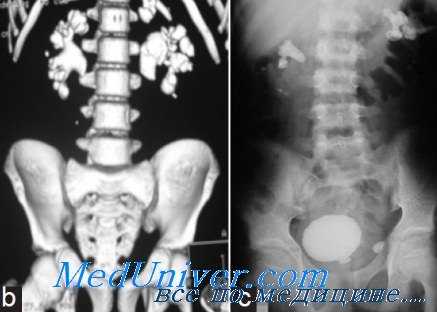

КТ и рентгенография при мочекаменной болезни (МКБ)

КТ ОБП и забрюшинного пространства. Плотные конкременты в нижних чашечках с обеих сторон. (фото Вишняков В.Н.)